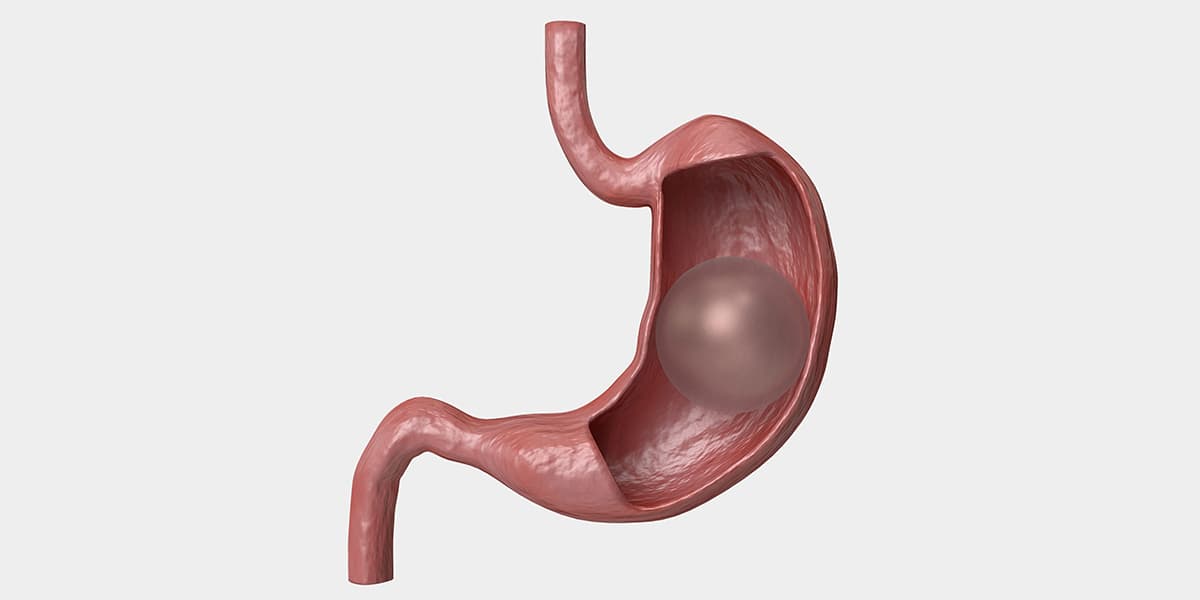

Endoskopik Obezite Tedavileri

Cerrahi olmayan yöntemlerle kilo verme sürecini destekleyen endoskopik uygulamalar.

- ✓Mide balonu uygulaması

- ✓Endoskopik sleeve gastroplasti

- ✓Metabolik sendrom yönetimi

- ✓Kişiselleştirilmiş tedavi planları